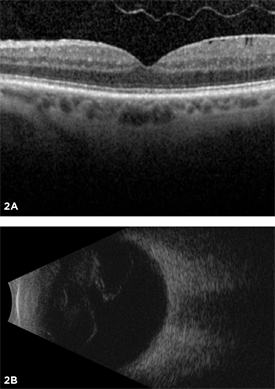

Posterior vitreous detachment is usually diagnosed with a dilated eye examination. However, if the vitreous gel is very clear, it may be hard to see the PVD without additional testing, such as optical coherence tomography (OCT) or ocular ultrasound (see Figure 2).

Figure 2. Most posterior vitreous detachments can be diagnosed with a dilated eye exam. However, OCT (A) and B-scan ultrasound (B) are diagnostic tests that can be helpful in diagnosing PVD.